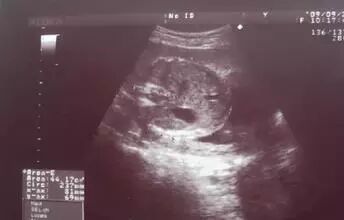

到怀孕六个多月时,突然出血了,量还很大。她的丈夫吓坏了,赶紧把她送到了医院。检查结果让她不敢相信——B超检查显示,子宫内充满了水泡状的东西,就跟葡萄一样,根本没有胎儿。

原来,这怀的是葡萄胎!医生说,它是指妊娠后胎盘绒毛滋养细胞增生,间质高度水肿,形成大小不一的水泡,水泡间相连成串,形状就像葡萄一样。发病率大约为1/1000。换句话说,就是胎儿没正常发育。

葡萄胎是指妊娠后胎盘绒毛滋养细胞增生,间质高度水肿,形成大小不一的水泡,水泡间相连成串,形如葡萄,亦称水泡状胎块(HM)。

葡萄胎分为两类:①完全性葡萄胎 胎盘绒毛全部受累,整个宫腔充满水泡,弥漫性滋养细胞增生,无胎儿及胚胎组织可见;